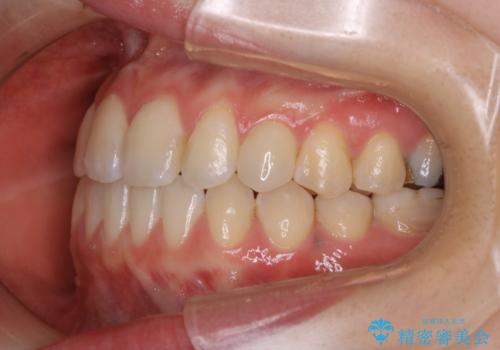

- 受け口で、前歯の嚙み合わせが気になるとの事でご相談にいらした方です。先天的に右上犬歯がなく、左上犬歯も小さい状態でした。矯正治療にて周囲の歯を動かして歯のスペースを確保した上で、被せものにて歯を作っていきました。

歯科技工士さんの熟練した技術により、周囲の歯としっかりなじむ天然歯のような被せ物をお作りすることが出来ました。

矯正治療と補綴治療をうまく組み合わせることで、美しい口元に仕上げることが出来ました。矯正治療、補綴治療をまとめて行える総合歯科治療を体現した治療といえます。